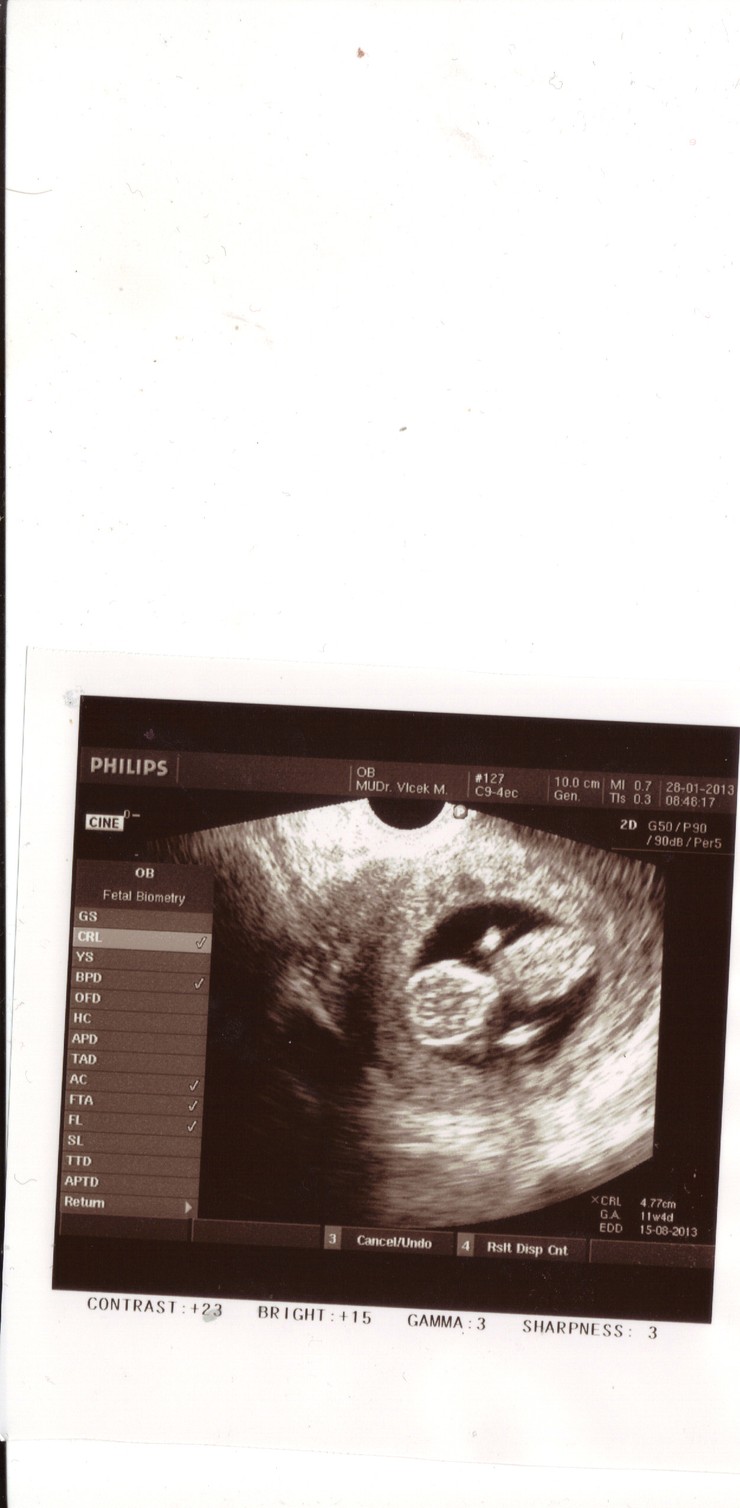

5 z 192

Niko a Patrik